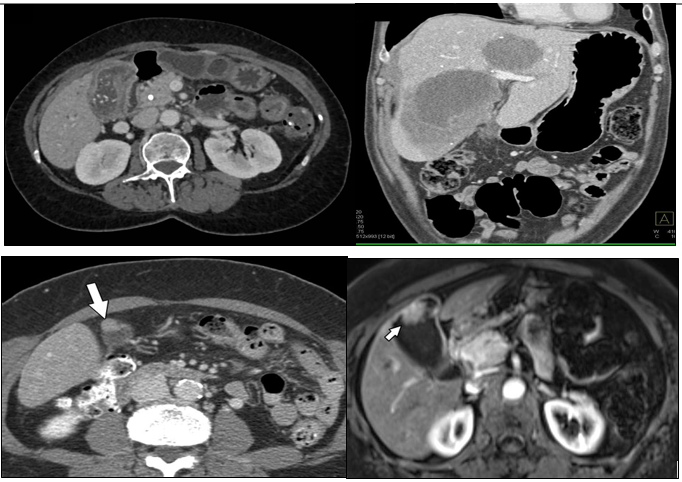

Fig 4: 1. Axial Contrast-Enhanced CT of Gallbladder Mass

• Shows a heterogeneously enhancing gallbladder mass invading adjacent liver segments—ideal for advanced-stage case visualization (Stage III–IV).

2. Coronal CT Demonstrating Liver Invasion

Displays contiguous spread into hepatic tissue, reinforcing AJCC staging importance.

3. CT Image Highlighting GB Wall Thickening

• Useful for illustrating diagnostic distinctions from adenomyomatosis (arrow pointing to irregular wall thickening).

4. T2-Weighted MRI of Gallbladder Carcinoma

• Excellent for depicting local extent and bile duct involvement in staging.